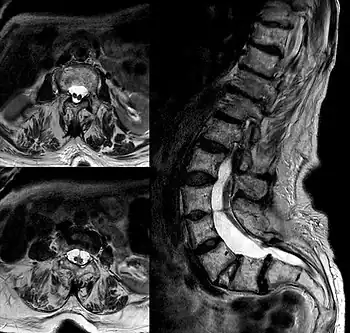

| Diastematomelia in MRI of lumbar spine. | |

Diastematomyelia (occasionally diastomyelia) is a congenital disorder in which a part of the spinal cord is split, usually at the level of the upper lumbar vertebra in the longitudinal (sagittal) direction. Females are affected much more commonly than males. This condition occurs in the presence of an osseous, cartilaginous or fibrous septum in the central portion of the spinal canal which then produces a complete or incomplete sagittal division of the spinal cord into two hemicords. When the split does not reunite distally to the spur, the condition is referred to as diplomyelia, which is true duplication of the spinal cord.[1]